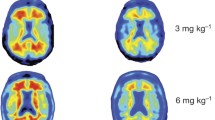

First, the specificity and relative affinity to Aβ were tested by measuring binding to immobilised Aβ 1–40 peptide. Figure 1b shows that both 3D6 and bind to recombinant peptide with relative high affinity (EC50 3D6 = 0.17 pM; EC50 chGantenerumab = 0.34 pM), however, 100-fold higher levels of mC2 were required to reach half maximal binding (EC50 mC2 = 17.4 pM), suggesting significantly lower affinity to immobilised Aβ. Antibodies were then tested for binding to Aβ plaques in brain sections from Tg2576 mice, and to better mimic in vivo binding conditions tissue sections were not subjected to any antigen retrieval before immuno-staining. 3D6 bound plaques in tissue obtained from Tg2576, while no binding was observed in wild-type mice. mC2 also bound but fewer plaques were labelled (Fig. 1c). chGantenerumab labelled plaques, however, it also appeared to bind to neurons in both Tg2576 and wild-type mice. All antibodies were produced as IgG2a isotype, using the same constant region, and therefore should all have the same ability to bind and activate FcγRs. We then tested the ability of these antibodies to bind to plaques in Tg2576 tissue sections with and without formic acid antigenic retrieval (Fig. 1e). Formic acid treatment breaks down aggregated Aβ into more soluble species. We found that 3D6 was able to bind to plaques without any antigen retrieval, but mC2 and chGantenerumab could not. After formic acid treatment, mC2 labelled plaques very well and chGantenerumab labelled them faintly. The conformation of Aβ in Tg2576 mice and human AD cases may be different, and this has previously been reported to affect target engagement of anti-Aβ antibodies [28]. To characterise the ability of antibodies to bind to Aβ from human cases, brain sections from AD cases were stained with and without formic acid antigenic retrieval (Fig. 1f). The results were comparable to Tg2576 tissue, with 3D6 able to bind plaques without antigenic retrieval, but staining improved after formic acid treatment. The antibody mC2 bound poorly without formic acid but labelled plaques well after treatment. chGantenerumab again showed background staining, but plaque binding was evident after formic acid treatment. Using an FcγR crosslinking assay, we tested the ability of each antibody to activate macrophages in vitro. All IgG2a anti-Aβ antibodies stimulate secretion of the cytokine TNFα compared to cell only controls, while mouse IgG1, a subclass which has lower affinity for activating FcγR, fails to induce TNFα secretion (Fig. 1d). In summary, 3D6 binds plaques and recombinant Aβ 1–40 peptide with high affinity and specificity, mC2 selectively binds Aβ but with lower affinity, while chGantenerumab binds Aβ 1–40 peptide with high affinity, in situ binding indicates non-specific binding to neurons. All antibodies have the comparable ability to activate macrophages through FcγRs.

In vitro binding and effector function of 3D6 chGantenerumab and mC2. a Purified recombinant antibodies were separated by reduced and non-reduced polyacrylamide electrophoresis. Non-reduced antibodies run as a single band, reduced antibodies break into heavy and light chain fragments (50, 25 kDa respectively). b Binding of anti-Aβ antibodies to immobilised Aβ 1–40. 3D6 and chGantenerumab both bind with relatively high affinity (EC50 3D6 = 0.17 pM; EC50 chGantenerumab = 0.34 pM) mC2 bound with lower relative affinity (EC50 mC2 = 17.4 pM). c Binding of 3D6, chGantenerumab and mC2 to Tg2576 (APP) and wild-type (WT) brain sections. d TNFα levels produced by RAW264.7 cells in response to immobilised Aβ antibodies or IgG1 control. Data analysed by one-way ANOVA and Tukey post hoc test, and expressed as mean pg/ml supernatant ± standard deviation (SD, n = 6). Data is representative of 3 independent experiments (****p < 0.0001). e Binding of antibodies to formalin-fixed tissue from Tg2576 mice, with and without formic acid antigenic retrieval. f Binding of antibodies to human AD brain tissue, with and without formic acid antigen retrieval